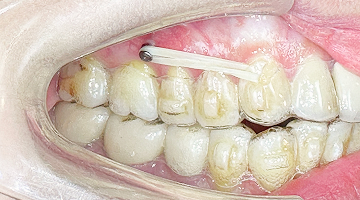

治療計畫中的紅色豆豆提供醫師方便看診

實際情況如左圖,較不明顯,近看還是有凸起感。